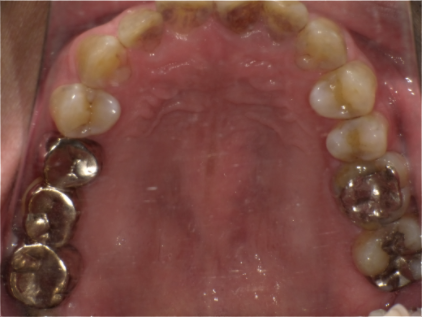

男性 症例内容 N様 30代

インプラント&咬合再構築及び根管治療も含めた全顎的修復症例

この患者様は営業のお仕事をされており、まだ30代と若いのに以前より歯に強いコンプレックスを持っておられました。

子供の頃に歯医者さんでかなり痛い思いをされたそうで、それ以来歯が悪いにも関わらず歯医者に行けず仕舞いだったそうです。

しかしこのままでは人前で歯を出して笑えない為仕事に差し障ると思い、一念発起しインターネットで調べ当院へ来院されました。そしてまず一本虫歯治療をして痛くなかった事を気に入られ当院で全額的に治したいと仰られました。

残せない歯は親知らずも含め6本抜き、欠損したところは計5本のインプラントにより補いました。

その他の虫歯が大きいとこは神経の治療をきっちりし、全ての歯をセラミックで回復しました。本人の希望でかなり白い色での回復となりました。

| 治療期間・回数 | 4か月・15回 |

| 費用(保険外診療) | 1本あたり 91,800円〜380,000円(税込)、総額5,001,000円 |

| 施術の副作用(リスク) | セラミック・仮歯が欠けたり、外れる事があります。インプラントの手術後は、まれに唇・舌・頬・歯肉・歯牙の感覚マヒが一時的に起こる場合もあります。また、近接歯牙・顎・上顎洞・鼻腔に対する炎症・疼痛・過敏症・組織治癒の遅延及び顔面部の内出血が避けられない方がまれにいます。術後、1〜4日立つと腫れ止めが切れるため傷口が腫れてきますが、殆どの場合は、1週間程度で傷口は治ります。 |